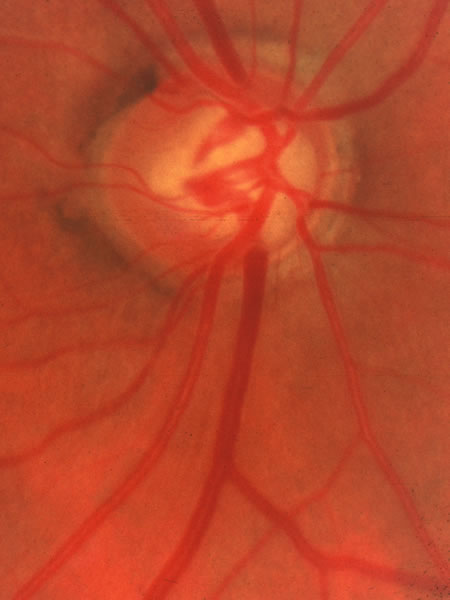

On the basis of family history, the intraocular pressure, the disc configuration, or the visual field, a patient may be diagnosed as having glaucoma, may be suspected possibly as having early glaucoma, or may be judged at risk of developing glaucoma. In any of these situations, it is wise to record the status of the discs with careful drawings or preferably (Figs. 18, 19, 39, and 40), if available, stereoscopic disc photographs. In addition, it is wise to record a carefully quantified visual-field examination (kinetic perimetry with several isopters or automated perimetry with a thresholding strategy) as a baseline.

Fig. 39. Glaucomatous disc photographed in 1992.

Fig. 40. Same eye photographed in 1998, after progression of the cupping and visual field loss. Continued thinning of the neuroretinal rim is evident in nearly every part of the circumference and the course of the veins across the inferior border of the disc show the deeper excavation. This progression would not likely be evident if only disc drawings were used to monitor the disc status. Stereoscopic fundus photographs of other forms of imaging are discussed in Chapter 48A are needed.